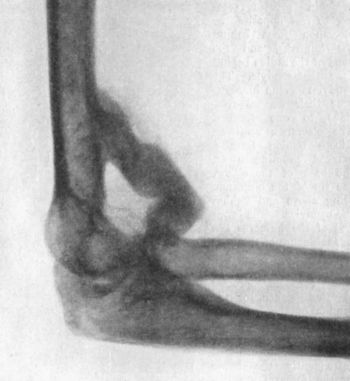

| 39. | Forward Dislocation of Elbow, with Fracture of Olecranon | 93 |

Osseous ankylosis is not a common sequel of simple fractures, but locking of joints from the mechanical impediment produced by the union of imperfectly reduced fragments, or from masses of callus, is not uncommon, especially in the region of the elbow.